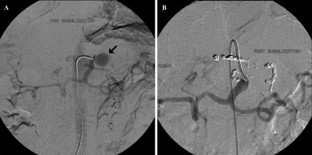

Ruptured Left Gastric Artery Aneurysm: Unique Presentation with Hemothorax and Hemomediastinum

Although splanchnic artery aneurysms are uncommon and remain mostly asymptomatic, they are associated with a high mortality rate when they rupture. We discuss the case of a 66-year-old woman who had successful embolization of a left gastric artery aneurysm after presenting with acute chest pain and the unusual computed tomography findings of hemothorax and hemomediastinum. To our knowledge, only one other similar case has been published in the literature.

Figure 1

Figure 2

Figure 3

Figure 4